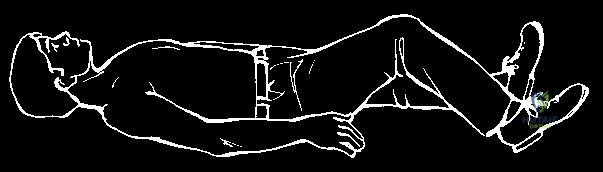

Acute posterior dislocations, conversely, demand immediate attention. Closed reduction should be attempted urgently, ideally within the first 48 hours, in a controlled environment such as the operating room with general anesthesia and cardiothoracic surgery available on immediate standby. The classic reduction maneuver involves placing a bump between the patient's scapulae, applying lateral traction to the abducted and extended arm, and utilizing a sterile towel clip to physically grasp the medial clavicle and lift it anteriorly. If closed reduction is successful, the joint is often stable, and non-operative management in a figure-of-eight harness or sling is appropriate. Operative intervention is strictly indicated when an acute posterior dislocation is irreducible by closed means, when it is highly unstable post-reduction, or when there are progressive signs of mediastinal compression (vascular compromise, dyspnea, dysphagia) that do not resolve with reduction attempts.

Patient positioning in the operating room requires meticulous attention to detail. The patient is placed in the supine position on a radiolucent operating table. A rolled towel or a specifically designed gel bump is placed vertically between the scapulae. This maneuver allows the shoulders to fall posteriorly, effectively opening up the anterior chest wall, retracting the lateral clavicle, and facilitating reduction of a posterior dislocation. The head is placed on a Mayfield horseshoe headrest or a standard foam donut, and the neck is slightly extended and rotated away from the operative side to maximize exposure of the sternocleidomastoid and the medial clavicular region.